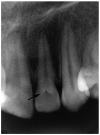

Results: Dens invaginatus was observed in 116 of 4556 subjects, with a frequency of 2.5%. There was only one periapical lesion in teeth with type I dens invaginatus, but 8.1% of patients with type II and 87.5% of patients with type III dens invaginatus had apical periodontitis at the time of referral. There were 116 (72%) females and 32 (27%) males with dens invaginatus.

Conclusion: This data represents the only study carried out in a large population in Turkey, and no dens invaginatus was found in mandibular teeth. The most commonly observed type of dens invaginatus was type I (69.8%).